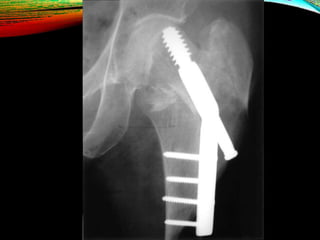

INTRAMEDULLARY HIP SCREW

Also known as the Proximal Femoral Nail (PFN).

Indications

• stable fracture patterns

• unstable fracture patterns

• reverse obliquity fractures (56% failure when treated with sliding

hip screw)

• subtrochanteric extension

• lack of integrity of femoral wall

Outcome

• equivalent to sliding hip screw for stable fracture patterns

• use has significantly increased in last decade

INTRAMEDULLARY HIP SCREW Alsoknown as the Proximal Femoral Nail (PFN). Indications • stable fracture patterns • unstable fracture patterns • reverse obliquity fractures (56% failure when treated with sliding hip screw) • subtrochanteric extension • lack of integrity of femoral wall Outcome • equivalent to sliding hip screw for stable fracture patterns • use has significantly increased in last decade